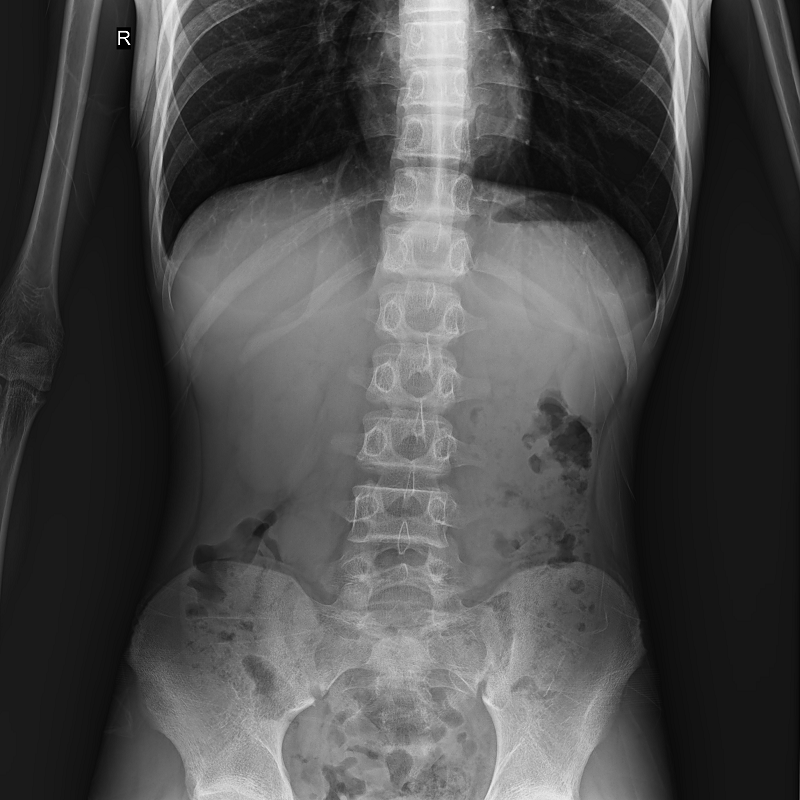

系統(tǒng)可以識(shí)別曝光圖像,無需設(shè)置識(shí)別點(diǎn)即完成精準(zhǔn)拼接,呈現(xiàn)大范圍完整影像。